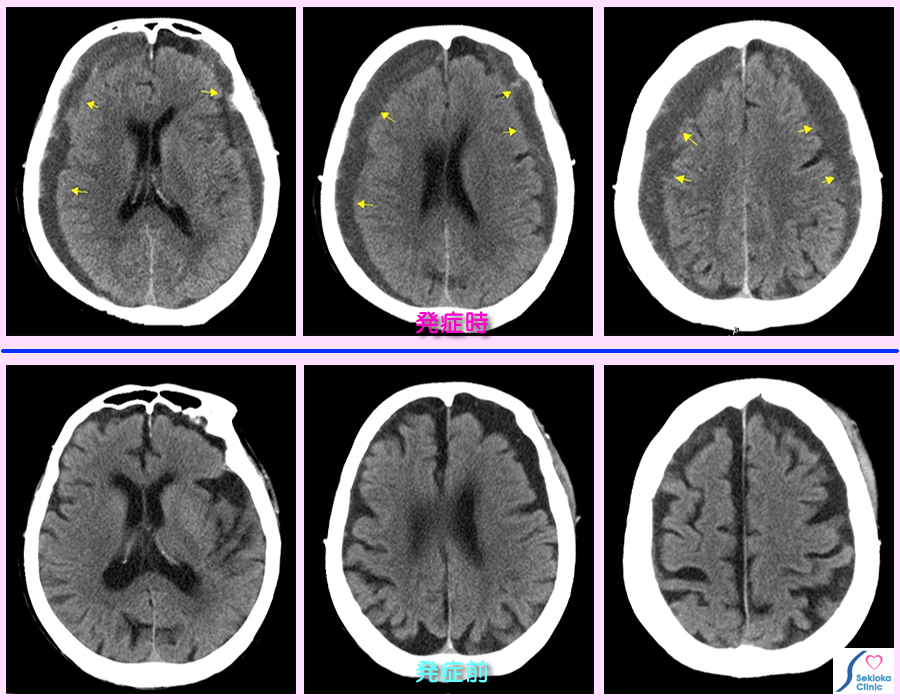

| 診断 | 主にCTで診断。脳表の片側または両側に三日月状に高X線吸収(画像では白く表示)または低吸収(黒く表示)領域として見られます。この表示の相異は出血のからの時間で変わります。血腫による圧排のため側脳室の狭小化や脳皮質溝の減少・消失も認められます(添付参考画像でも発症前と後で側脳室の狭小化、脳溝の減少が認められます)。掲載例は100歳の患者さんで最近、反応が鈍くなり,痴呆の急速な進行様の症状から本症を疑いCT撮影をおこなった例です。高齢のため著明な脳萎縮があり頭蓋骨と脳皮質の間の隙間が以前からありますが、以前の下段の画像と比べると変化が明瞭です。両側に水腫を認め、やや白く認められる部位(X線吸収値が高い)は出血を示唆すします。 |